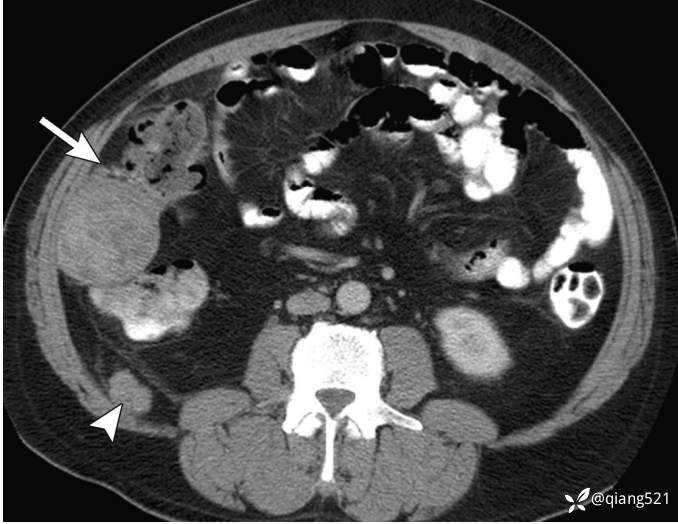

48岁男子,患有网膜梗死;对比增强CT显示网膜脂肪滞留、血管聚集和螺纹外观的局灶性区域(箭头)